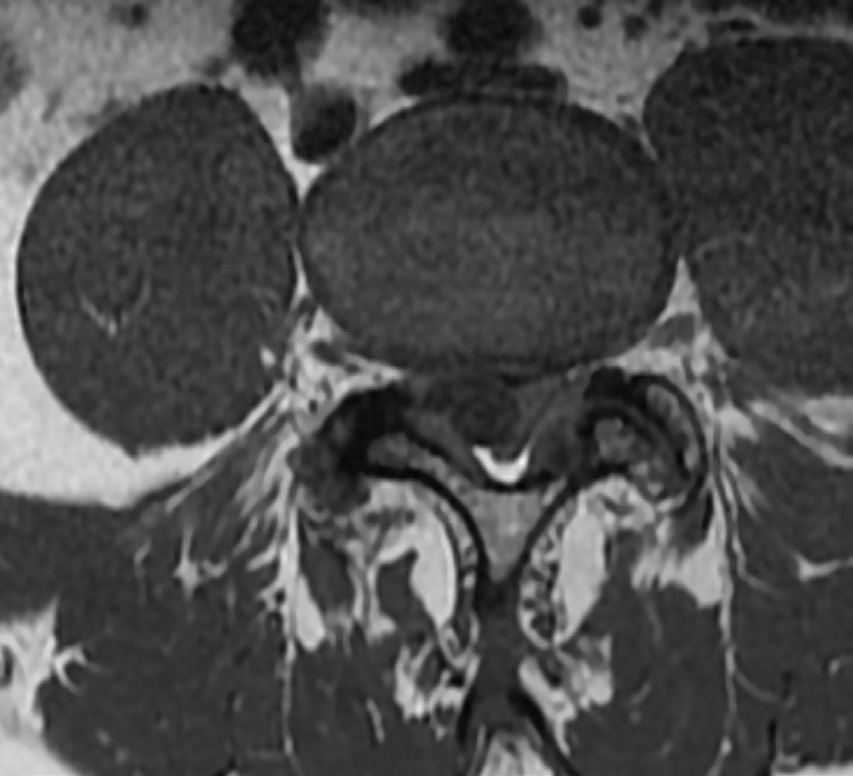

- RM lumbar inicial: condrosis degenerativa L2-S1, con abombamiento discal leve L4-L5 y quiste sinovial en la faceta articular derecha L4-L5, provocando estenosis severa del canal raquídeo.

- RM de control: resolución casi completa del quiste sinovial en L4-L5, con cambios degenerativos persistentes en articulaciones interfacetarias y discos desde L2 a S1.

Quiste sinovial facetario derecho en L4-L5 asociado a estenosis severa del canal raquídeo con resolución espontánea.

El dolor mejoró en un 90% en las semanas posteriores, logrando casi completa resolución sintomática. Al compararse estudios de RM, se evidencia la desaparición significativa del quiste sinovial. Paciente asintomático y en seguimiento por Atención Primaria.